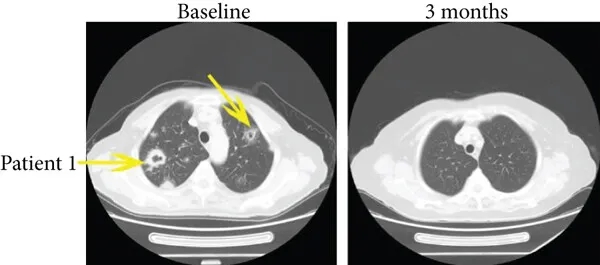

值得关注的是两例完全缓解的典型患者:

病例1为一例35岁患者,治疗前伴随肺转移,接受免疫联合治疗3个月后,多发性肺转移灶完全消失(详见下图,黄色箭头所示),PFS达15.4个月。

▲图源“J Immunol Res”,版权归原作者所有,如无意中侵犯了知识产权,请联系我们删除